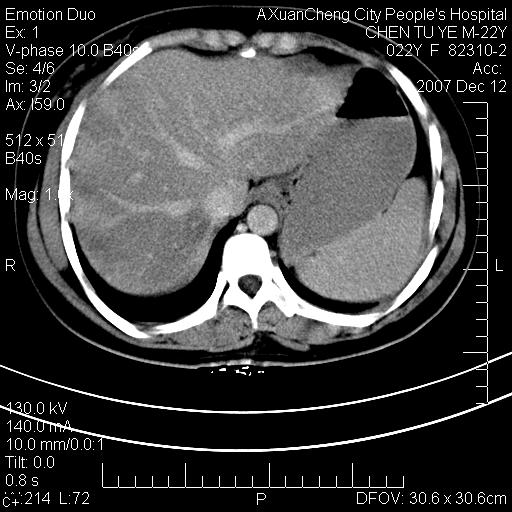

超声提示肝右前叶占位,约2.5cm.

各位战友看看病灶在什么地方,可是右前叶进肝裂部低密度影,平扫ct值约10以下,增强后增高明显

脂肪肝.楼主所指部位不考虑异常,为肝圆韧带影.

不均匀脂肪浸润,版主所说的病灶为肝园韧带服着点。

考虑肝圆韧带。